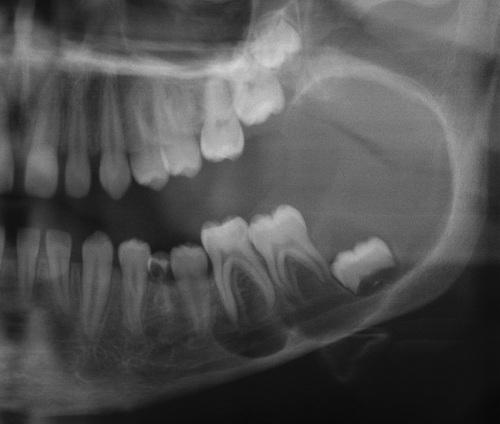

Radiographic Features

- well-defined radiolucent area

- large lesions may appear multilocular

- smooth and often corticated margins

- growth in an anteroposterior direction

- may involve an unerupted tooth (25% to 40%)

This large, multilocular cyst involves most of the ascending ramus and is growing in an anteroposterior direction.

odontogenic keratocyst (OKC)